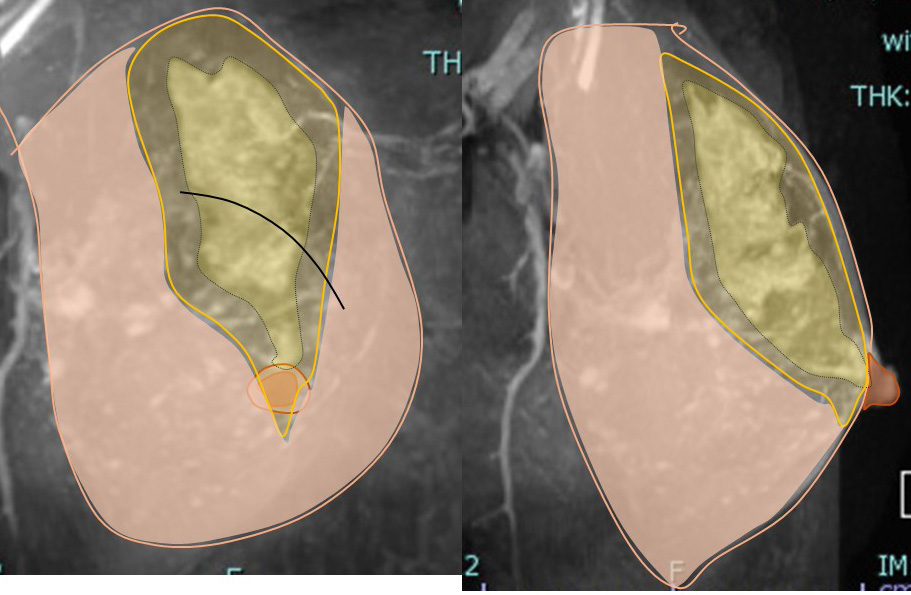

拡がりに対してマージンをつけた切除範囲はこうなります。

↓

皮切、この場合には弧状切開とすると

癌をマージンをつけて摘出します。 (無論「皮膚」も「乳頭」も切除しません)

引っ張ってきて(寄せて)縫合します。

何故ここまで引っ張れるかって?

それは乳腺が立体的(厚みを持っている)からです。

乳腺に厚みがあるから引き延ばせて縫合できるのです!